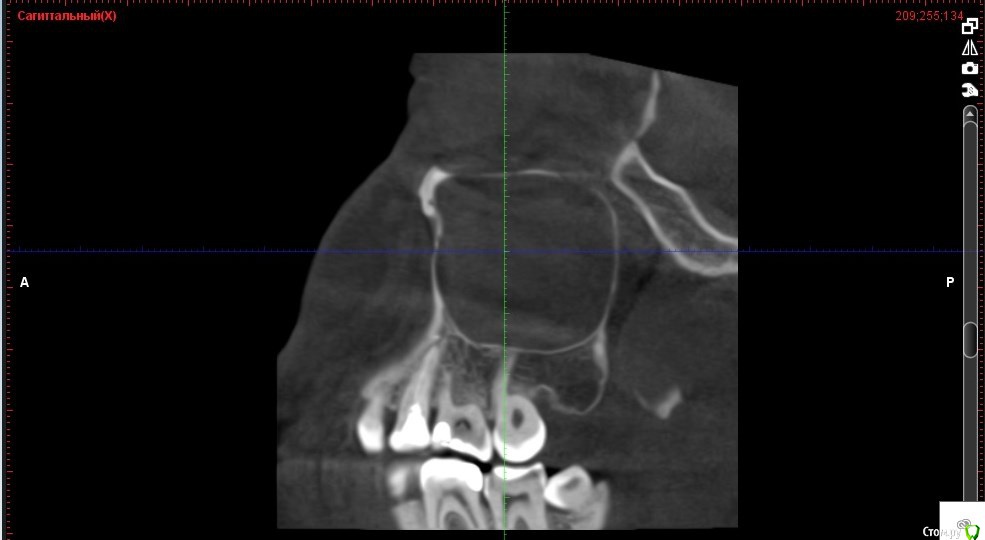

Verasss Опубликовано 8 октября, 2016 Автор Поделиться Опубликовано 8 октября, 2016 КТ от 08.09. Извините, что в таком виде, надо менять ОЗУ. Ссылка на комментарий

DmitrySH Опубликовано 8 октября, 2016 Поделиться Опубликовано 8 октября, 2016 В таком виде КТ малоинформативно. Но гайморита нет. Ссылка на комментарий

Verasss Опубликовано 28 октября, 2016 Автор Поделиться Опубликовано 28 октября, 2016 Добрый вечер! Ещё раз попытаюсь прикрепить скриншоты КТ от сентября. Если качество совсем не устраивает, подскажите, пожалуйста, какие сделать снимки?К сожалению, программа не позволяет вывести снимки на полный экран и заскриншотить в более хорошем качестве. Ссылка на комментарий

Verasss Опубликовано 28 октября, 2016 Автор Поделиться Опубликовано 28 октября, 2016 еще снимки Ссылка на комментарий

Verasss Опубликовано 28 октября, 2016 Автор Поделиться Опубликовано 28 октября, 2016 и еще Ссылка на комментарий

Verasss Опубликовано 23 ноября, 2016 Автор Поделиться Опубликовано 23 ноября, 2016 Сделала ещё 1 кт, спустя почти 2,5 месяца после первого. Посмотрите, пожалуйста, есть ли изменения? Напомню, что пункцию гайморовой мне сделали. Ссылка на комментарий